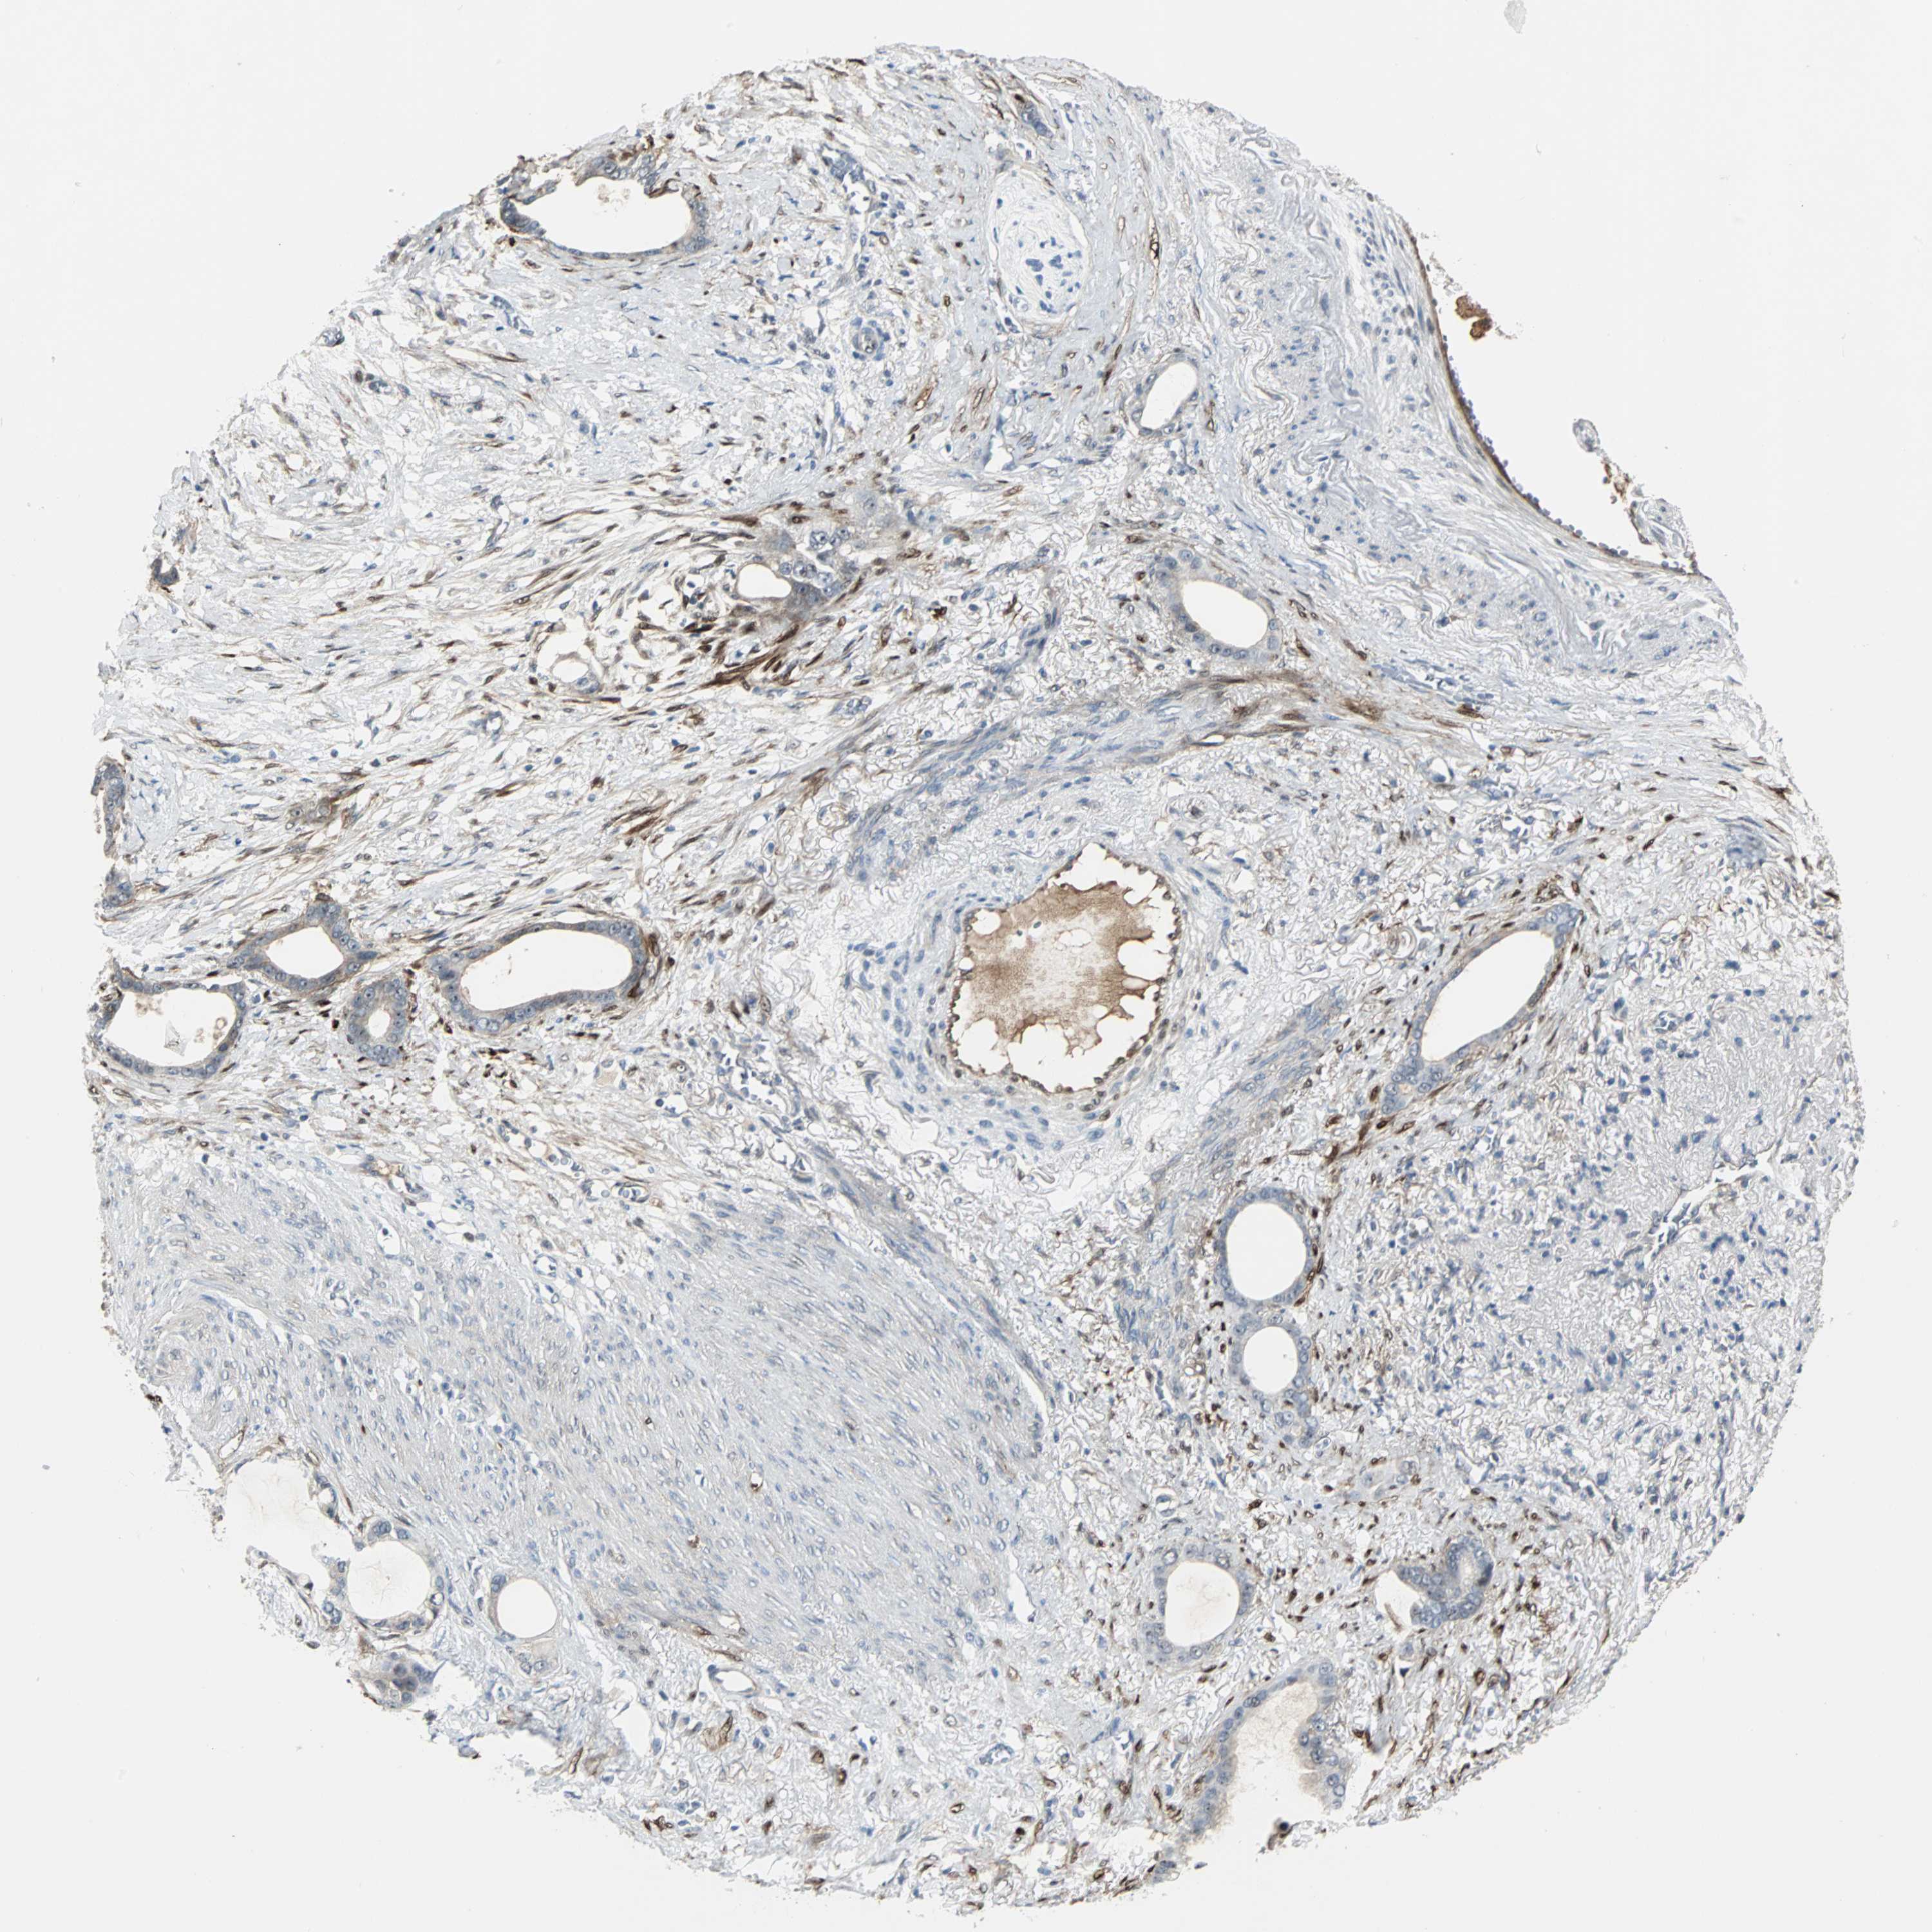

STOMACH CANCER - Protein expressioni

A mouse-over function shows sample information and annotation data. Click on an image to view it in a full screen mode. Samples can be filtered based on level of antibody staining by selecting one or several of the following categories: high, medium, low and not detected. The assay and annotation is described here.

Antibody stainingi

Antibody staining in the annotated cell types in the current human tissue is reported as not detected, low, medium, or high, based on conventional immunohistochemistry profiling in selected tissues. This score is based on the combination of the staining intensity and fraction of stained cells.

Each image is clickable and will lead to virtual microscopy that enables deeper exploration of all samples and also displays staining intensity scores, fraction scores and subcellular localization as well as patient and tissue information for each sample.

Antibody HPA005922

Antibody HPA006028

Antibody CAB008368

Staining

High

Medium

Low

Not detected

Intensity

Strong

Moderate

Weak

Negative

Quantity

>75%

75%-25%

<25%

None

Location

Nuclear

Cytoplasmic/membranous

Cytoplasmic/membranous,nuclear

Adenocarcinoma, NOS

Adenocarcinoma, High grade